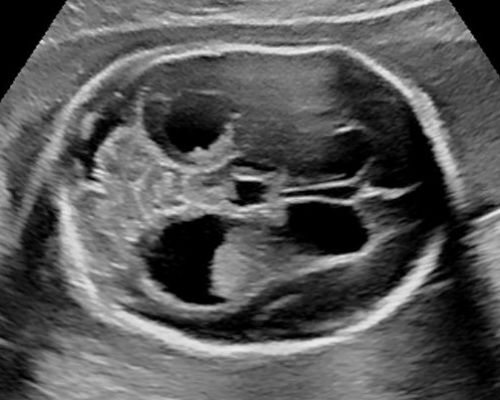

Sono-Online - fetale Fehlbildungen: "Gehirn"

Sonoanatomie, Biometrie, Hinweiszeichen & Diagnose von Entwicklungsstörungen, Kasuistiken, ausreichend Zeit für Diskussionen, Fallbeispiele aus der Praxis (Quiz)